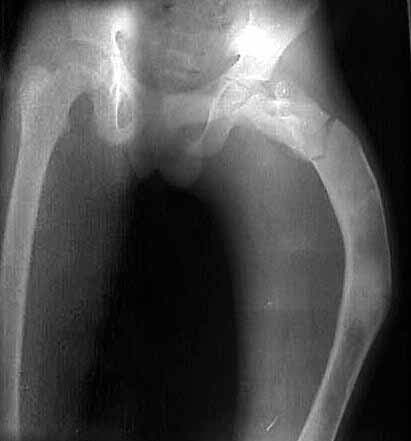

I am seeking help in managing a young patient 14 years old male with pathological subtrochanteric fracture neck femur. the problem is the severe varus deformity of the proximal femur the so called shepherd's crook deformity and also healing fracture shaft femur in midshaft region which he had sustained 6 months ago and was treated conservatively elsewhere. patient wants his deformity correction along with his fracture treatment if possible.

photo

no txn